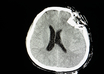

Long-studied protein could be a measure of traumatic brain injury